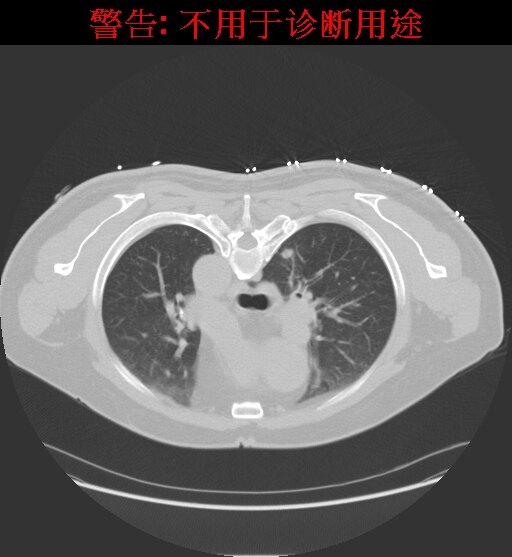

CT引导下精准穿刺将射频电极至于结节中央,设定消融直径15mm,设定消融温度90,治疗10分钟